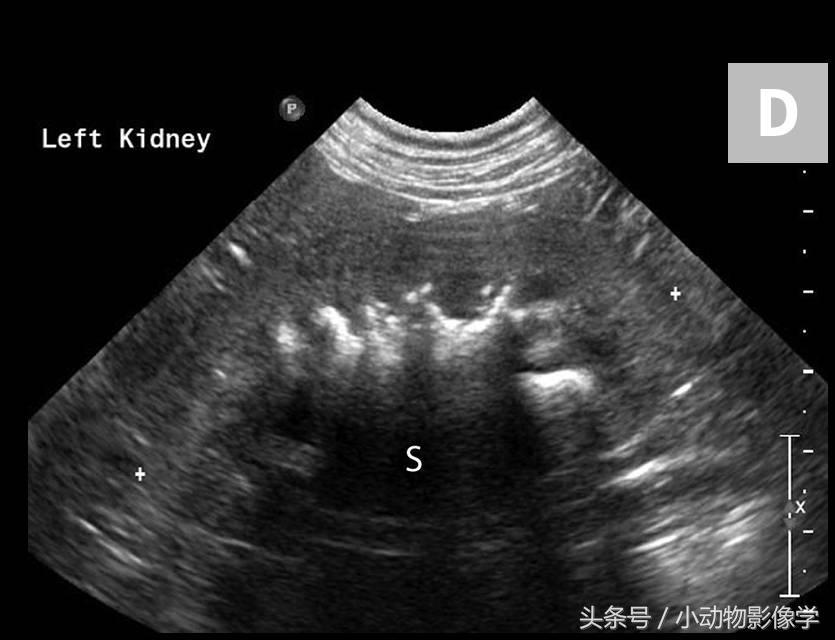

图3C、这是另一只临床表现正常的犬X光片,这张类似的左肾影像的特写图片中可见边缘不规则的结石和营养不良矿化的肾憩室区域(肾憩室上成对的矿化不透明的粗线条)。

图3D、图3C中左肾的超声图像。注意不规则边缘,肾憩室相关的营养不良矿化的线性区域,导致明显的远端声影。图像上的阴影伪像(S)使得我们难以评估那些在X光片上容易看到的解剖结构。可将这张图像与图1B中的正常肾脏进行比较。